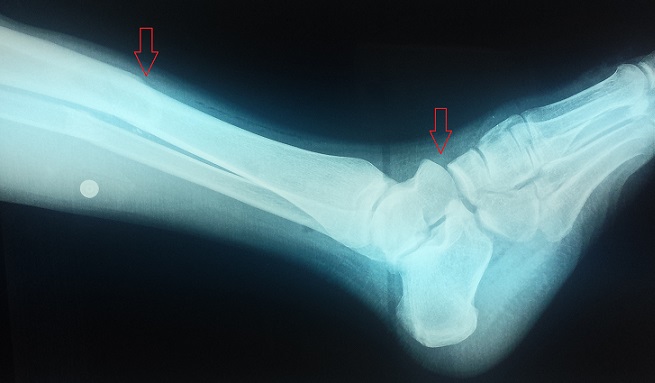

Un patient de 22 ans se présente aux urgences pour une impotence fonctionnelle douloureuse et immédiate du pied gauche suite à un accident de la voie publique. L'examen clinique montre une vive douleur du tiers inférieur de la jambe, avec une cheville oedématiée sans ouverture cutanée. Les diagnostics à évoquer sont une fracture bimalléolaire ou une fracture du quart distale de jambe. Le bilan radiologique de la jambe face et profil ainsi que du trois-quarts déroulé du pied a objectivé une fracture transverse du tiers inférieur des deux os de la jambe gauche associée à une luxation homolatérale plantaire de l'articulation de chopart, soit une « cheville flottante ». Classiquement, une cheville flottante associe une fracture distale de jambe à une fracture du pied ipsilatérale créant ainsi une instabilité autour de la cheville laissant la mortaise intact. La luxation de l'articulation médiotarsienne (AMT) plantaire reste rare en raison des fortes structures ligamentaires en particulier le ligament plantaire, long et court, le ligament bifurqué et le ligament calcanéonaviculaire plantaire comme support de l'arche du pied. La luxation de l'articulation médiotarsienne plantaire est encore plus rare lorsqu'elle est associée à une fracture de jambe. Les chevilles flottantes sont des lésions rares, se présentant souvent dans le cadre de traumatismes ouverts, et dont le pronostic fonctionnel reste réservé. Le traitement se base sur l'immobilisation provisoire du membre traumatisé avant d'avoir recours à une ostéosynthèse adéquate des deux lésions.